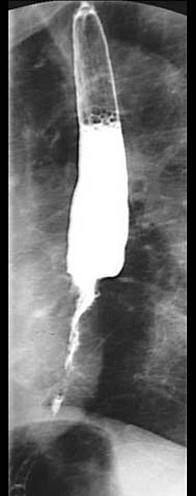

问题 男,60岁,进行性吞咽困难半年,左锁骨上有数枚2cm直径的肿大淋巴结,质硬,不能推动,X线钡餐检查如图所示,其治疗应首选是 ( )

选项 A、放疗后再行手术切除 B、多次输血,保守治疗 C、放射疗法 D、化学疗法+食管内记忆合金支架植入后放疗 E、争取手术切除

答案 D